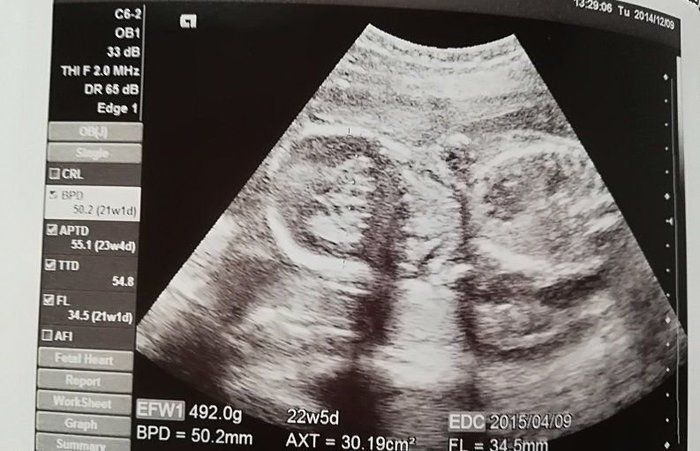

rainyさんの妊娠22週目のエコー写真 性別を教えてもらいました

エコー写真はこちらを向いた“がい骨”のようでした。まだ脂肪が付いていないので痩せて見えるようです。腹囲が91.5cmもありました。何処から見ても立派な妊婦さんです。医師に性別が分かるか聞いたら「男の子みたいですよ」と言われました。女の子を期待していたので、かなりショックを受けたのを覚えています。今となれば、男の子はかわいくて息子に申し訳ない気持ちです。赤ちゃんの推定体重は943gでした。